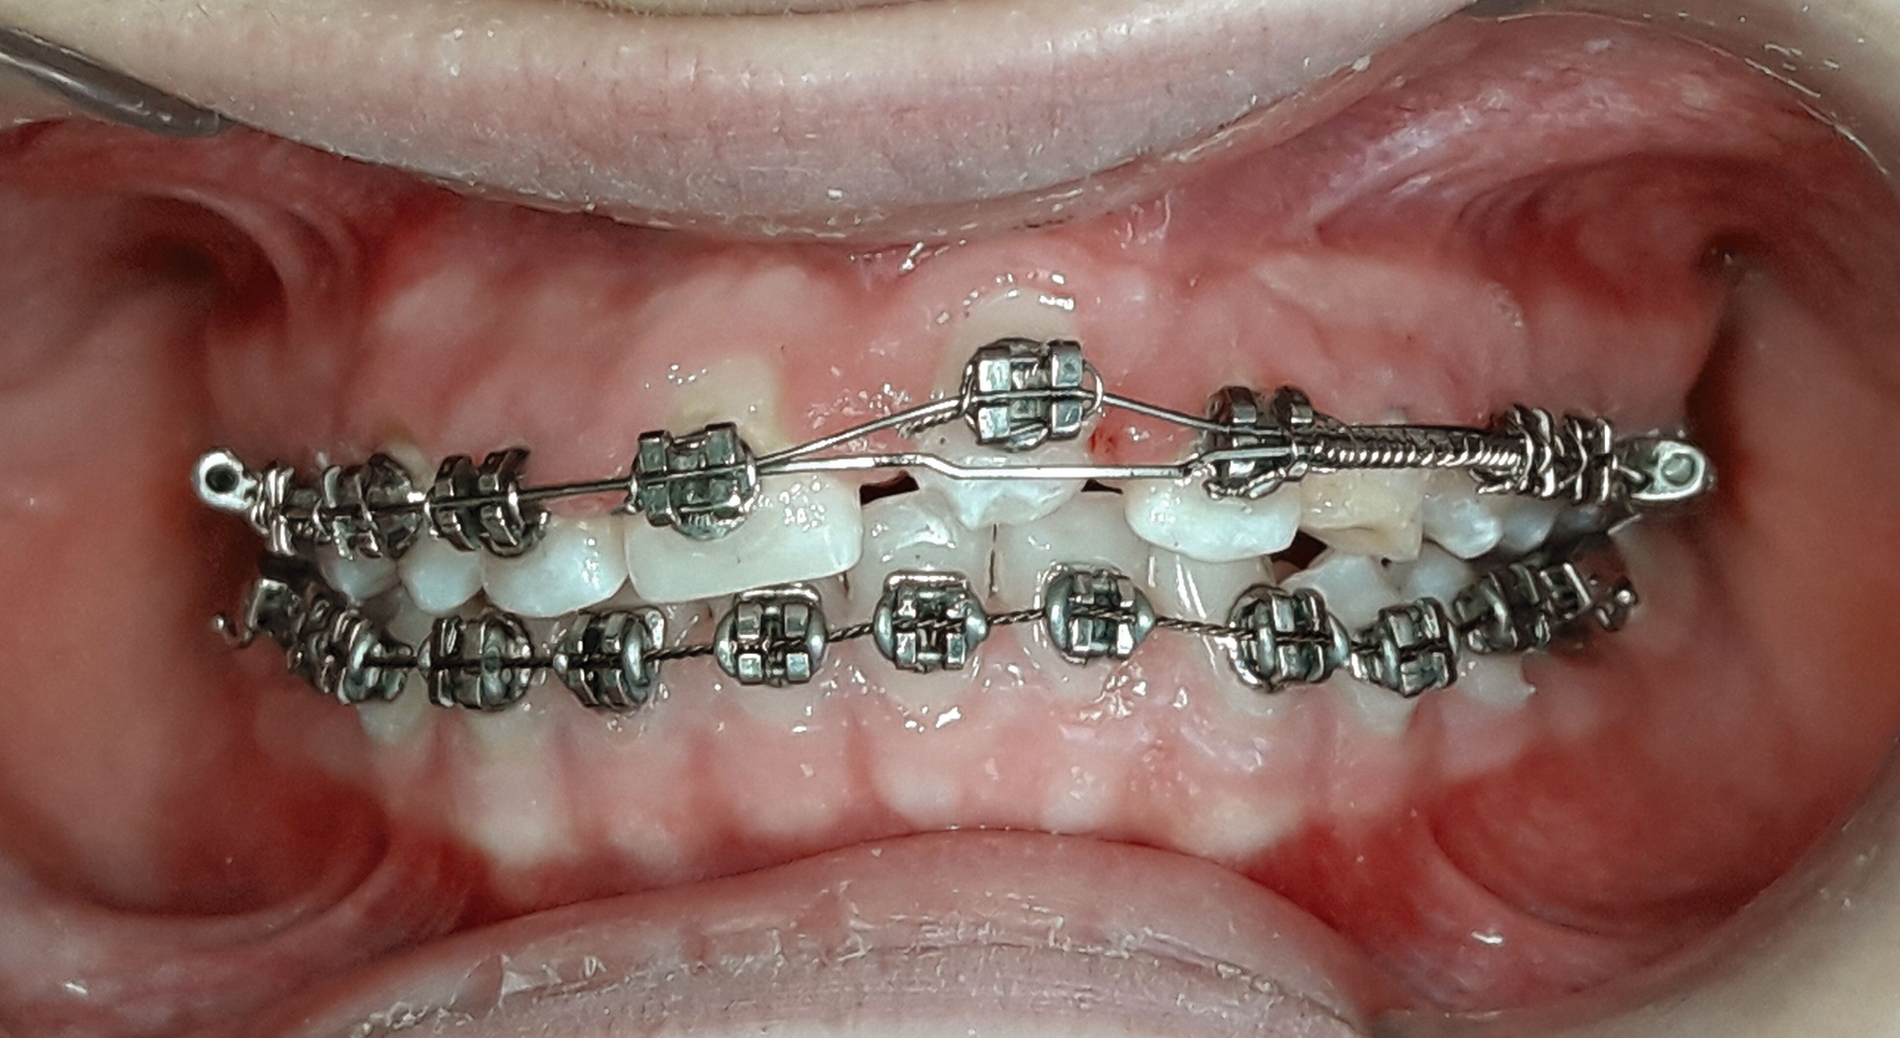

Sechzehn Monate später wurden die Brackets im Unterkiefer geklebt. Als der linke Eckzahn im Bereich des linken mittleren Schneidezahns durchbrach, wurde der Knopf mit dem Draht durch ein Bracket ersetzt. Der Eckzahn wurde mit der Huckepack-Technik extrudiert und eine Druckfeder zwischen den Zähnen 22 und 24 eingesetzt, um die Breite der Lücke Regio 23 anzupassen (Abbildung 5). Bei der Huckepack-Technik werden üblicherweise flexible, superelastische Drähte in Kombination mit einem steiferen Basisbogendraht verwendet, um die Einordnung verlagerter Zähne zu ermöglichen und die Wirkung reaktiver Kräfte hinsichtlich der horizontalen und der vertikalen Verankerung zu begrenzen.